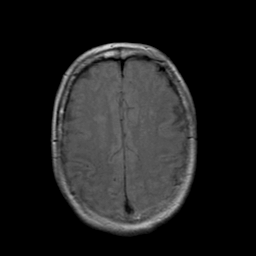

Stroke: proton density-weighted MR #2 -- Slice #18

[Home][Help][Clinical] Slice 18